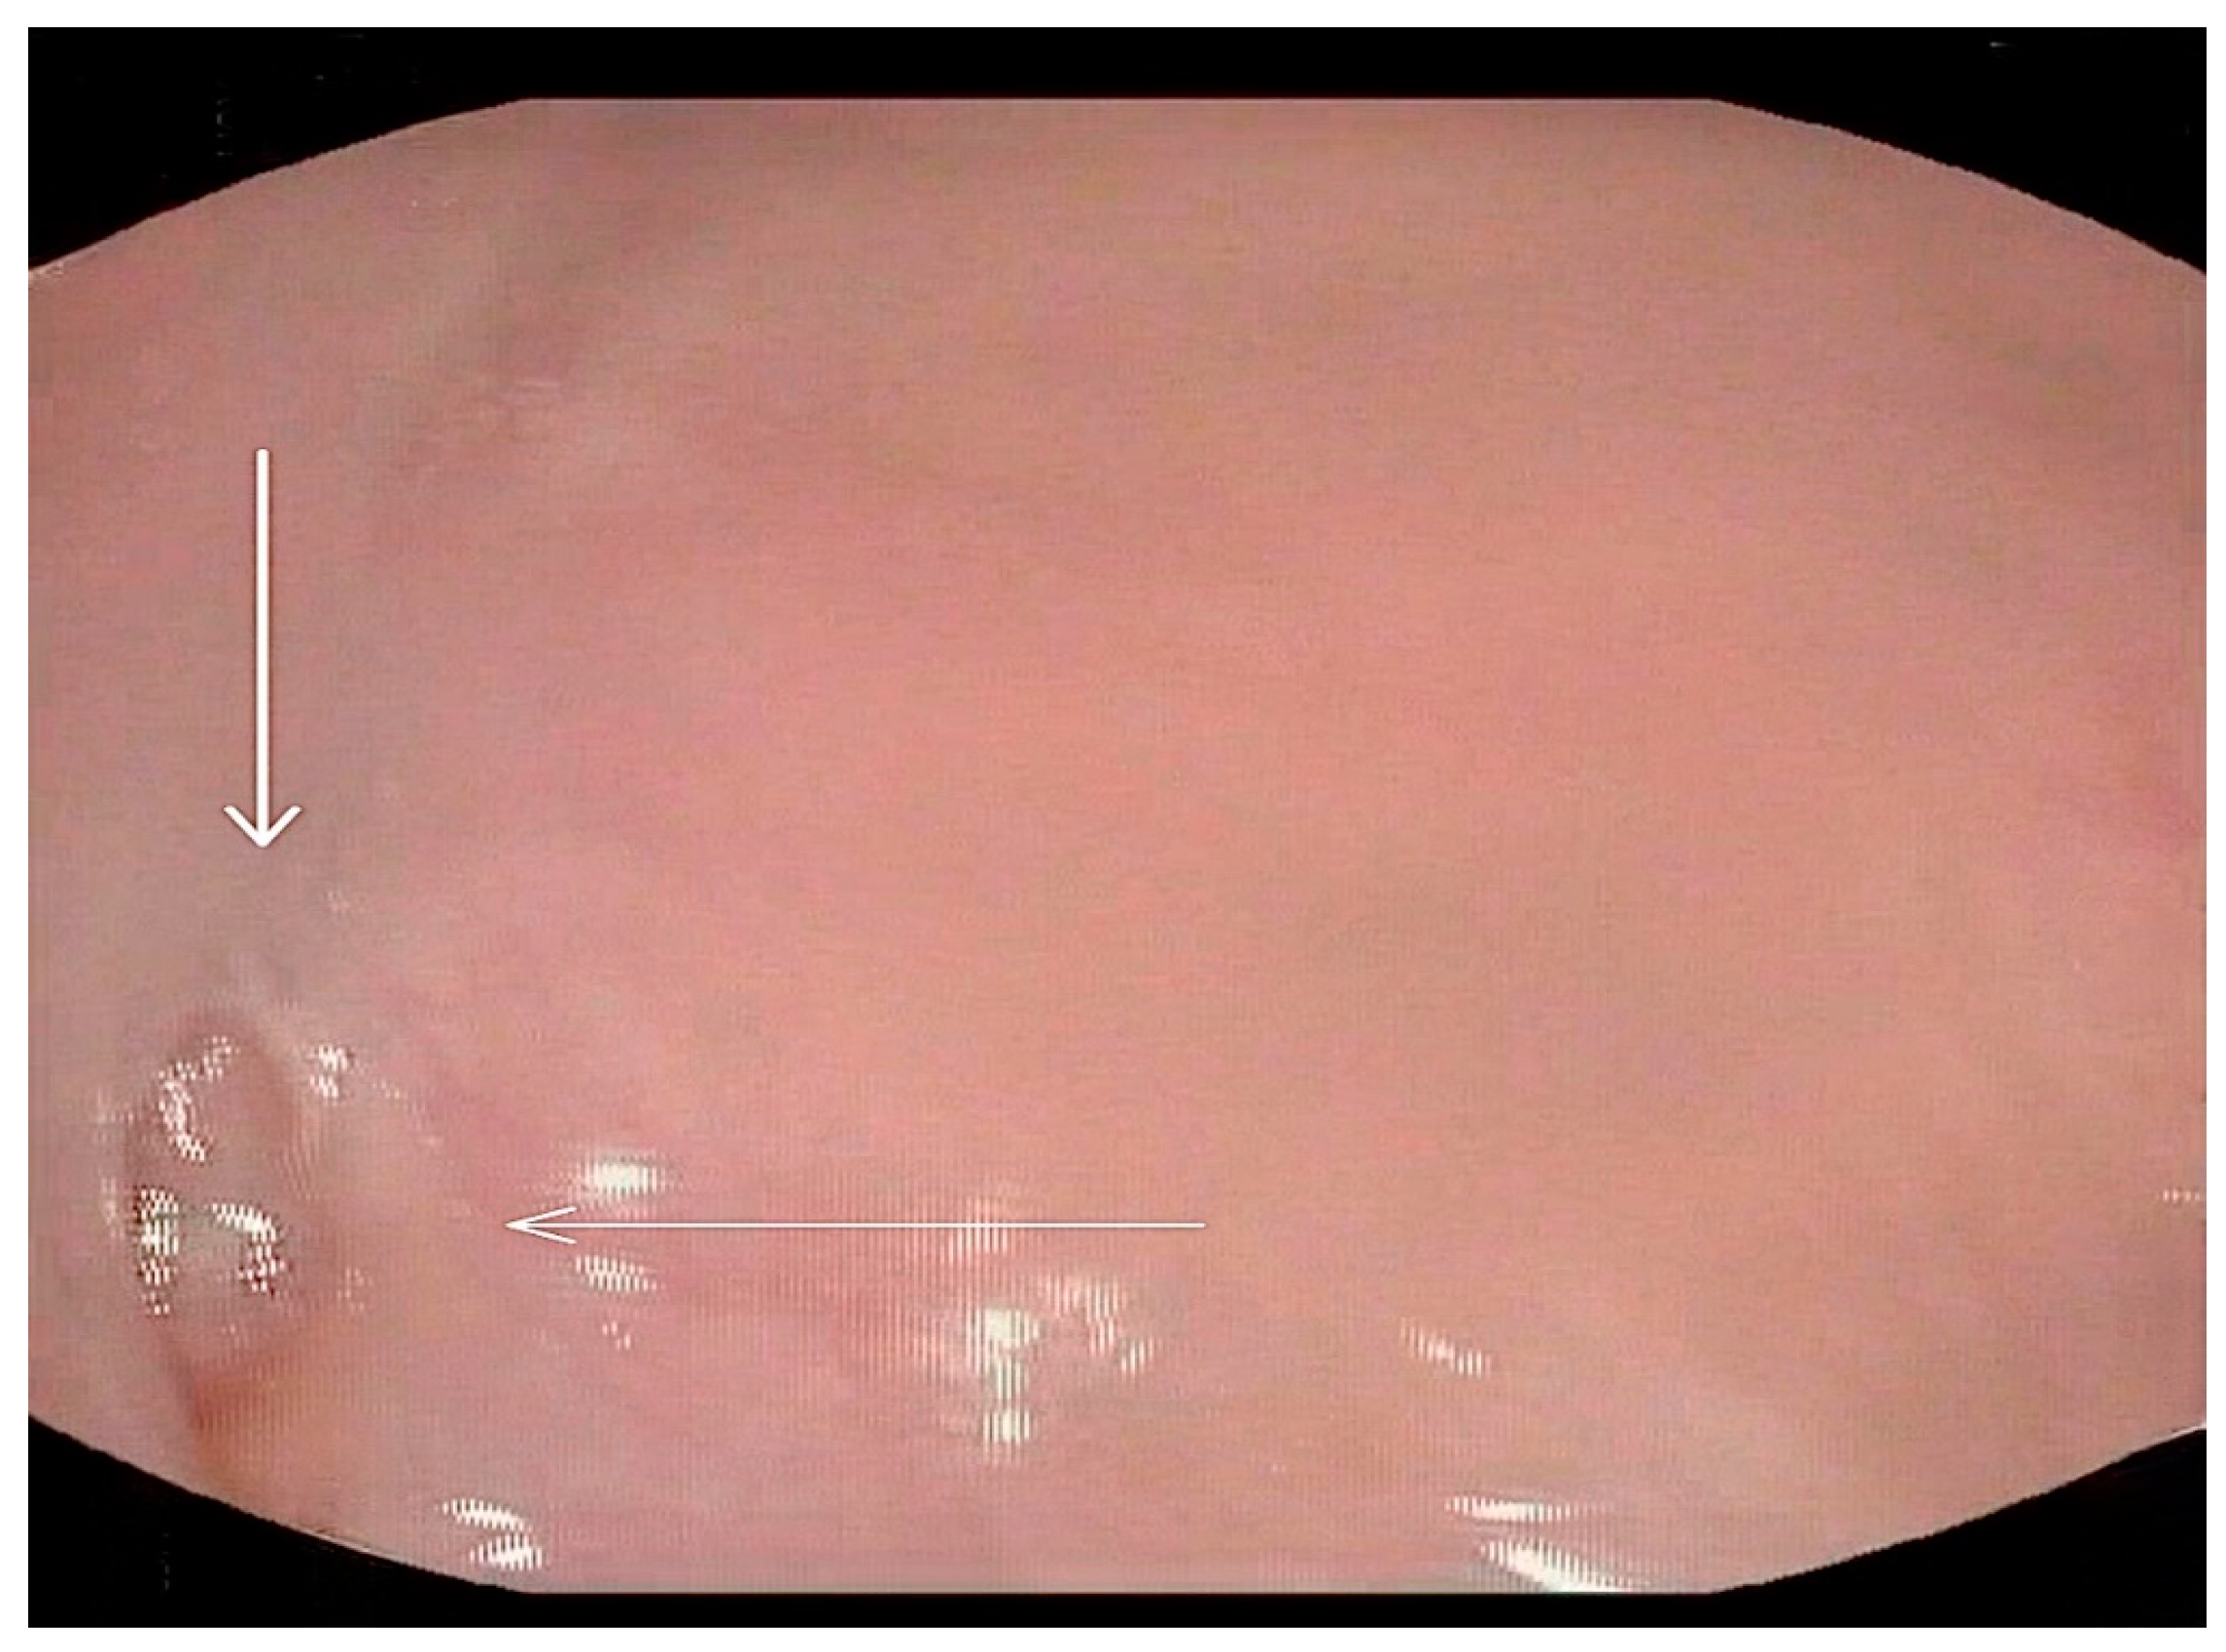

• A videofluoroscopic swallowing study (VFSS) was conducted to assess the oral, pharyngeal, and esophageal stages of swallowing with lateral and anteroposterior views using liquids of thin, thick, and pureed consistencies. The study, conducted by an SLP and a radiologist, showed two posterior inferior oral pouches (buccal diverticula) clearly seen on the floor of the mouth after swallowing. Moreover, two posterior pharyngeal wall pouches (diverticula) in the oropharynx at the level of the second cervical vertebra were visualized (Figure 1 and Figure 2) in addition to regurgitation and flaccid epiglottis. However, no aspiration or penetration was seen during the study.

Figure 1. Selected still images from VFSS, lateral view: bolus pooling and residual contrast in (A). buccal diverticula and (B). pharyngeal diverticulum.

Figure 2. Selected still images from VFSS, lateral view: simultaneous bolus pooling and contrast residue in (A) two buccal and (B) two pharyngeal diverticula.